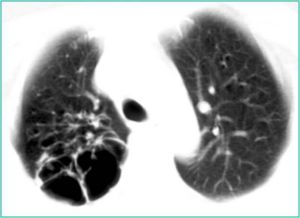

3.胸部X線診斷

(1)右下肺動脈乾擴張:橫徑>=1.5cm。經動態觀察後動脈乾橫徑增寬達2mm以上。

(2)肺動脈段凸出,高度>=3mm。

(3)中心肺動脈擴張與外周分支纖細兩者形成鮮明對比,呈“殘根狀”。

(4)右前斜位圓錐部凸出高度>=7mm。

(5)右心室增大(結合不同體位判斷)。具有(1)至(4)項中兩項以上或(5)1項者可診斷。

①肺部變化:隨病因而異,肺氣腫最常見。②肺動脈高壓表現:肺動脈總乾弧突出,肺門部肺動脈擴大延長及肺動脈第一分支。一般認為右肺動脈第一下分支橫徑≥15mm,或右下肺動脈橫徑與氣管橫徑比值≥0.17,或動態觀察較原右肺下動脈乾增寬2mm以上,可認為有該支擴張。肺動脈高壓顯著時,中心肺動脈擴張,搏動增強而外周動脈驟然變細呈截斷或鼠尾狀。③心臟變化:心臟呈垂直位,故早期心臟都不見增大。右心室流出道增大時,表現為肺動脈圓錐部顯著凸出。此後右心室流入道也肥厚增大,心尖上翹。有時還可見右心房擴大。心力衰竭時可有全心擴大,但在心力衰竭控制後,心臟可恢復到原來大小。左心一般不大,偶見左心室增大。心電圖查